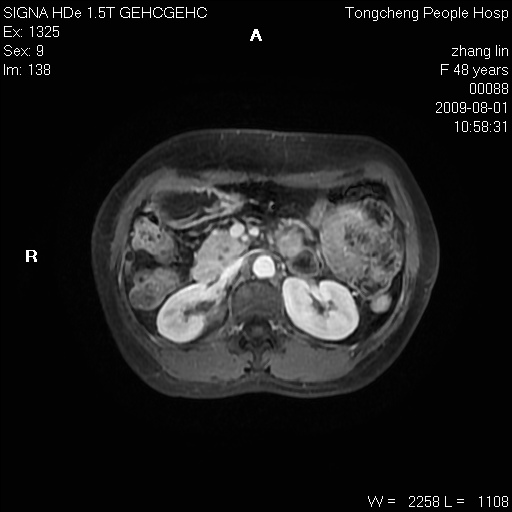

女,48岁。健康体检,彩超发现右肾占位性病变。平素健康。

临床诊断:右肾占位性病变,性质待定(囊肿?肿瘤?)。

上中腹部mr平扫+增强扫描,图像如下:

右肾上极见一类圆形病灶,t1wi呈等信号t2wi呈等高混杂信号,三期增强无强化,边界清---考虑囊肿出血。

同反相位均表现为等信号,病变无强化,考虑含蛋白的囊肿可能,弥散加权相或许有些帮助,